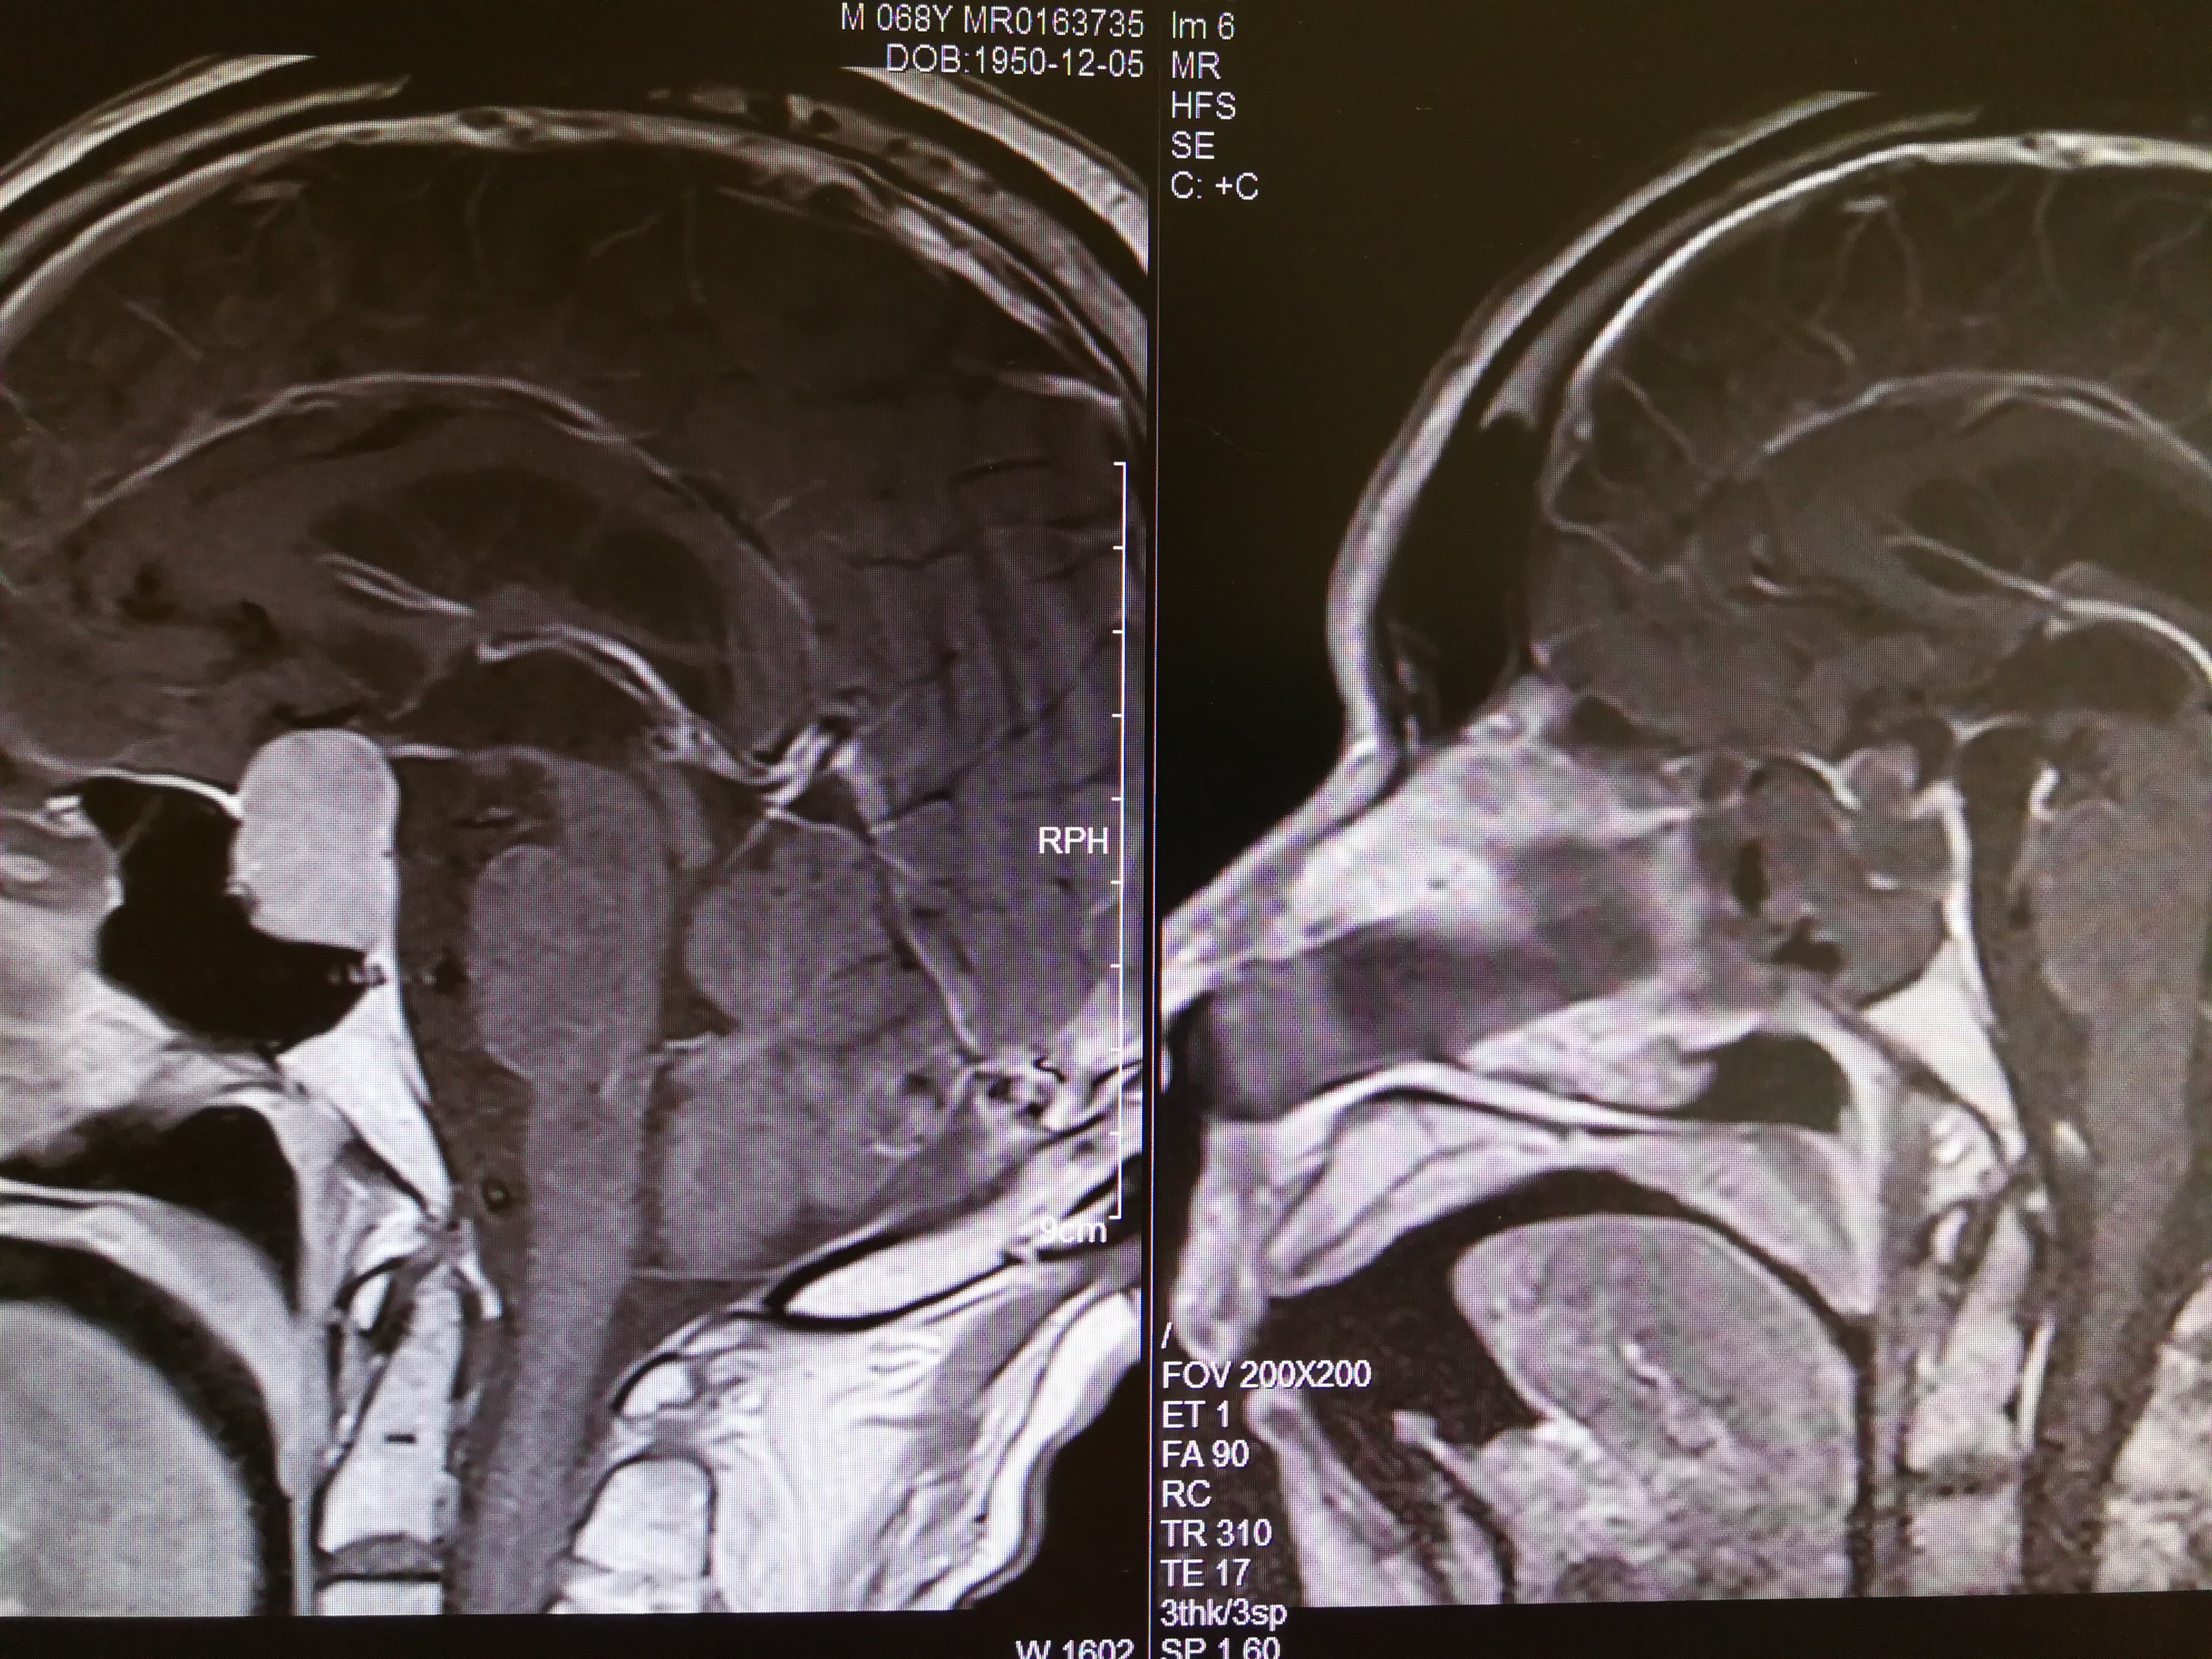

术后(右)核磁共振片,手术效果满意,病人恢复得也很好,希望垂体瘤患者